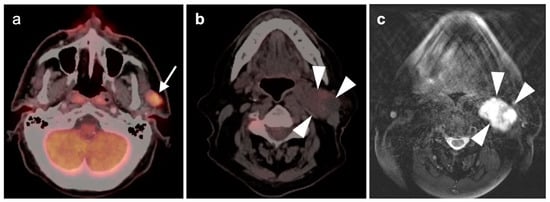

2.3. Nasopharyngeal Carcinoma

- Mohandas, A.; Marcus, C.; Kang, H.; Truong, M.-T.; Subramaniam, R.M. FDG PET/CT in the management of nasopharyngeal carcinoma. AJR Am. J. Roentgenol. 2014, 203, W146–W157. [Google Scholar] [CrossRef]